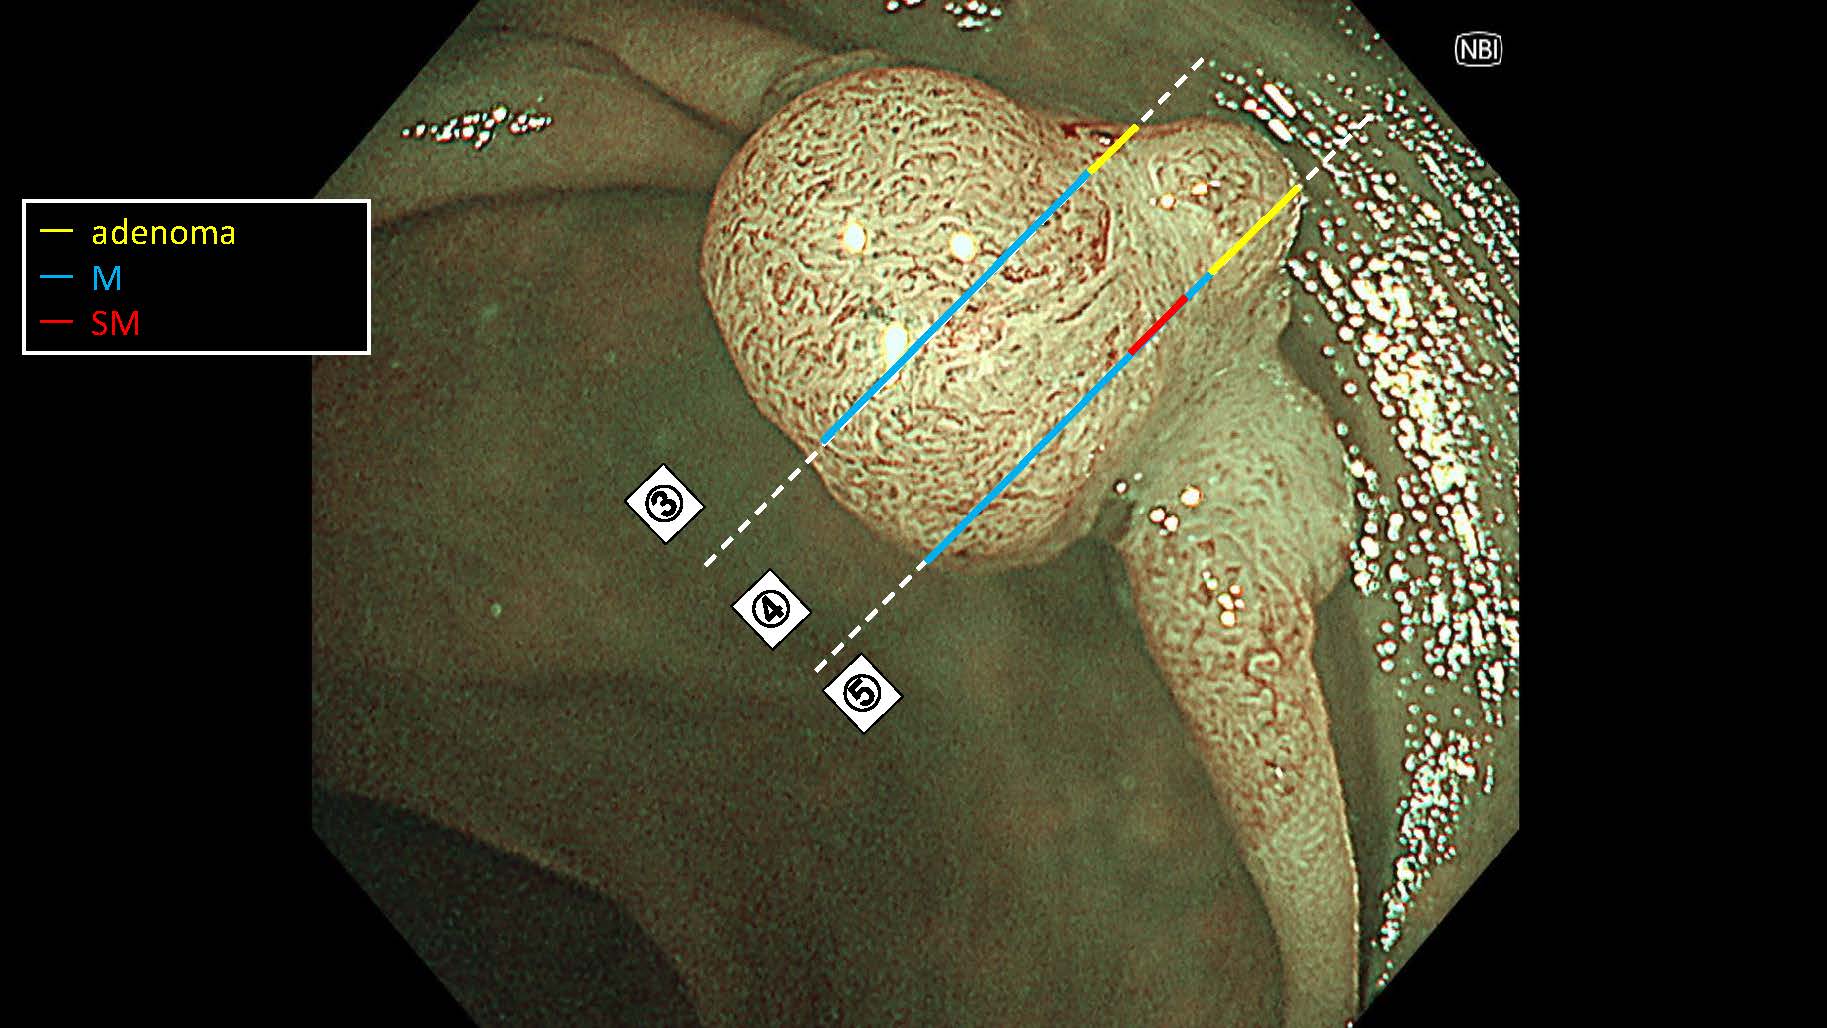

消化管Mapping~大腸~ 2025.6.11

内視鏡検査・治療

消化管Mapping